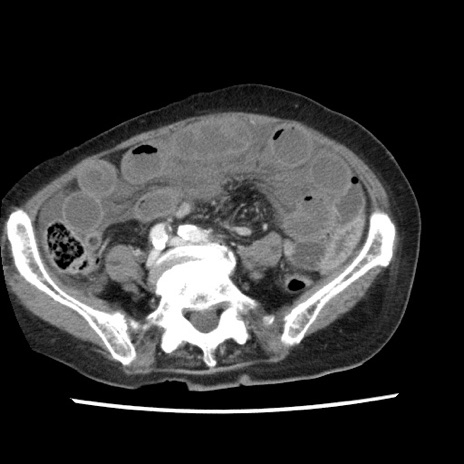

症例1(横断像)

【症例】80歳代女性

【主訴】腹痛

【現病歴】8時間前から腹痛あり来院。

【既往歴】糖尿病、脂質異常症、子宮体癌にて子宮全摘術

【身体所見】意識清明・会話良好だが腹痛で苦悶様、全腹部にわたって反跳痛と圧痛あり

【データ】WBC 13600、CRP 0.14、LDH 224、CK 90